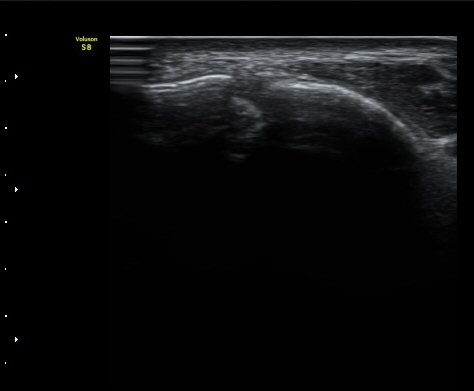

¹ß¸ñ°üÀý ¾Õ Á¾´Ü¸é°Ë»ç¿¡¼­ ¼Ò·®ÀÇ ¼ö¾×Àú·ù°¡ °üÂûµÈ´Ù(±×¸² 1, 2).